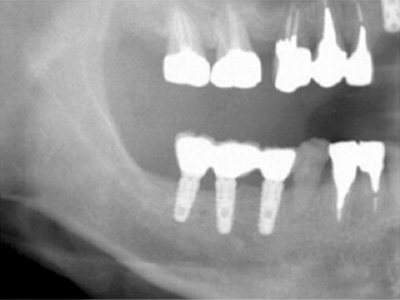

40代女性。上顎前歯を抜歯、虫歯と歯槽膿漏の状態が悪く、抜歯されたのですが、歯を支える歯槽骨が大きく吸収されてしまっていました(黄色矢印)。

インプラント治療を希望されていたのですが、下顎骨の中を通る神経(赤色矢印)が近接していて、骨が不足しているためインプラントの埋入が困難な状況でした。 -

患者様の智歯の辺りから、患者様ご自身の骨を採取し、移植した後のレントゲン写真です。

採取した骨片を、小さなチタン製のスクリューで固定してあります。

これが遊離自家骨移植術です。 -